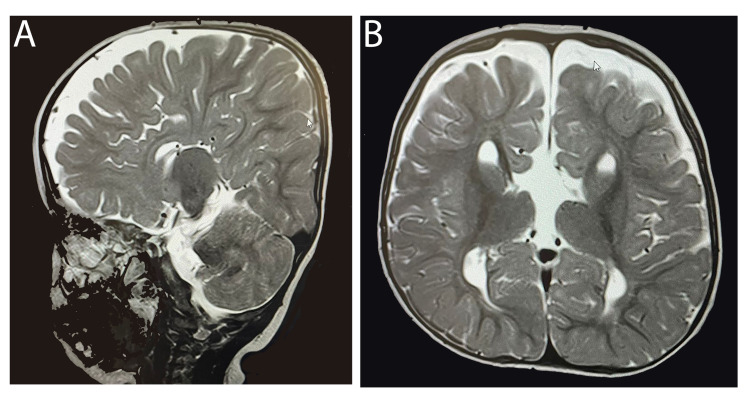

一名 14 个月大的女童,有全身发育迟缓、畸形特征(眼距过远、眼球突出、上睑下垂、小颌畸形)和弱视病史,被转诊至佳学基因遗传病罕见病基因检测案例协作单位。就诊原因是言语和语言发育迟缓。 她的父母是一级近亲,被诊断患有双侧重度至极度SNHL,并在 9 个月大时安装了双侧助听器。 然而,在随访中没有发现使用助听器有明显的好处。 磁共振成像 (MRI) 显示胼胝体有效发育不全(图 1)。 此外,全外显子组测序显示 LRP2 基因突变,证实了 DBS 的诊断。 在 18 个月大时,她的智商测试成绩为 75 分。

病例 1 的 MRI:(A) 矢状切面 (B) 冠状切面显示胼胝体有效发育不全